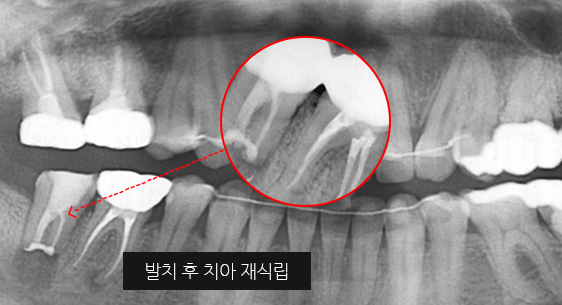

심한 염증으로 치조골이 광범위하게 소실, 아래쪽 신경관이 가까이 있어 치근단수술이 불가능한 상태, 타 병원에서 임플란트 진단을 받았지만, 고운미소치과에서 치아를 발치하고 뿌리 쪽 염증을 제거한 후 발치한 치아를 다시 심는 치아재식술을 시행하였습니다.

기존 신경치료 부위에 염증과 치조골이 소실되고 있는 상태

치아를 발치하고 염증을 제거, MTA로 충전하고

치아를 다시 심음. (난이도 중)